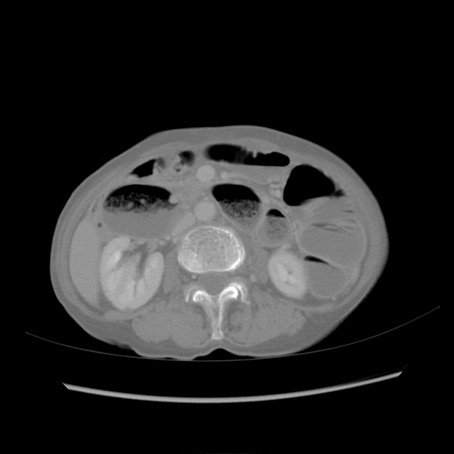

冠状断像

【症例】80歳代女性

【主訴】胸のつかえ感

【現病歴】約9時間前に食後から胸のつかえた感じあり、嘔吐あり、来院。

【既往歴】胃癌(全摘)、胆摘、虫垂炎

【身体所見】心窩部に圧痛あり、反跳痛なし。

【データ】WBC 5700、CRP 0.05